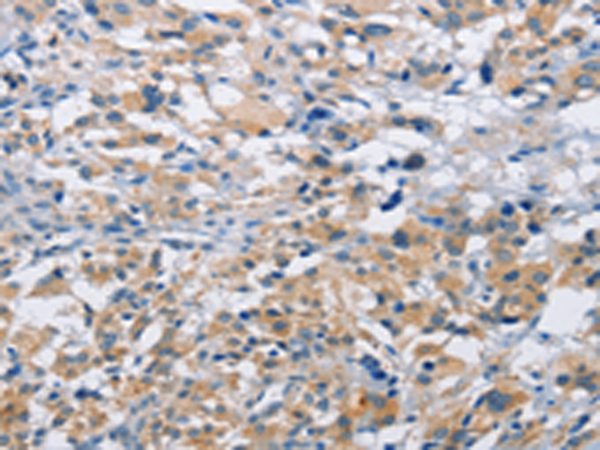

IHC positive control: |

Human thyroid cancer and human liver cancer |